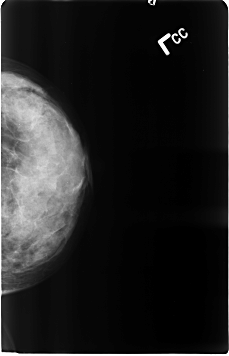

B_3120_1.LEFT_CC

LEFT_CC LINES 4624 PIXELS_PER_LINE 2976 BITS_PER_PIXEL 12 RESOLUTION 50 NON_OVERLAY